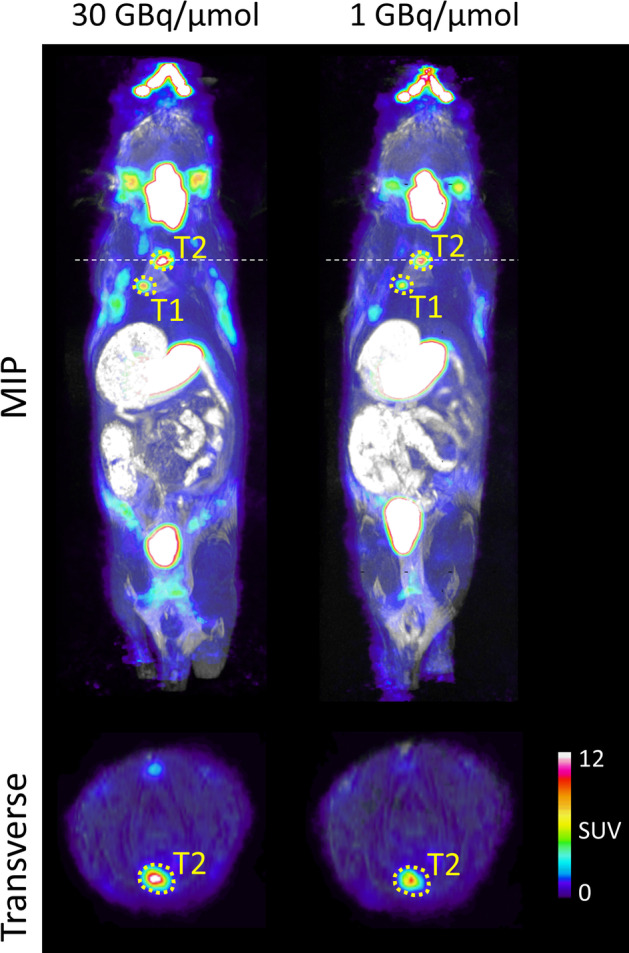

PET/MRI images of a mouse harbouring NIS-expressing lung tumours were acquired on two consecutive days following injection of [18F]TFB either of high (30.4 GBq/µmol) or low (1 GBq/µmol) molar activity at the time of injection. Low molar activity was achieved by adding a pre-calculated carrier amount of tetrafluoroborate into the final formulation to adjust the molar activity to the desired value at the reference time (Fig. 5).

Fig. 5.

A maximum intensity projection (MIP) and transverse plane are shown on the PET/MRI of the same NIS expressing lung tumour model mouse imaged on two consecutive days, injected with 30.4 GBq/µmol (left) and 1 GBq/µmol (right) [18F]TFB.

Two tumours were identified on the PET/MRI images, their SUVs and corresponding change in SUV intensity are reported in the Table 4along with SUVs of the thyroid gland (an organ expressing endogenous NIS (Jauregui-Osoro et al. 2010)).

Table 4.

Standardised uptake values and their relative change in NIS expressing tumours and thyroid in mice injected with high (30 GBq/µmol) and low (1 GBq/µmol) molar activity

| ROI | SUV, High Am | SUV, Low Am | SUV decrease (%) |

|---|---|---|---|

| Thyroid | 43.8 | 33.8 | 22.9 |

| T1 | 8.5 | 7.3 | 14.3 |

| T2 | 15.4 | 10.7 | 30.6 |

We were able to identify multiple small lung tumours with high [18F]TFB uptake as early as day 48 after tumour induction (Fig. 5); high tumour-to-normal lung contrast was observed. Further, we were able to follow lung tumour development longitudinally by performing repeated imaging (Fig. 8).

To demonstrate if high molar activity [18F]TFB preparation had effect on the imaging properties of the tracer we have compared SUVs from the NIS expressing tumours and thyroid in a mouse injected with high and low molar activity (Fig. 5; Table 4). On average 22.6% decrease was observed. We recognise limitations of drawing any conclusions from single mouse image, nevertheless our recent study (Dzien 2022) performed with the [18F]TFB formulation prepared according to the procedures published in this report has proven its suitability for the NIS gene reporter imaging in mice.